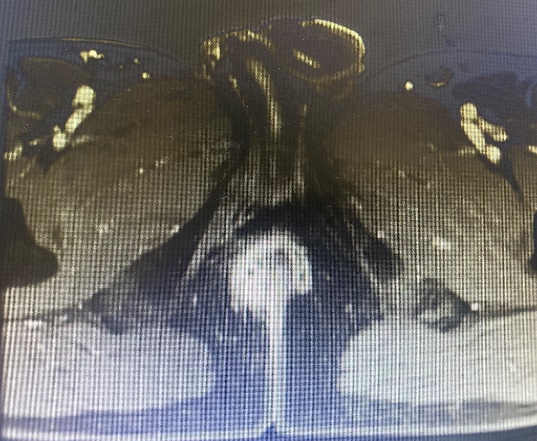

rhm5

Ảnh 5: Hình ảnh đường RMN trên phim MRI

Bệnh nhân được nội soi đại trực tràng và chụp phim cộng hưởng từ tầng sinh môn cho kết quả có đường rò hậu môn hình móng ngựa, có 1 lỗ rò trong ở vị trí 6h, 6 lỗ rò ngoài ở xung quanh hậu môn.